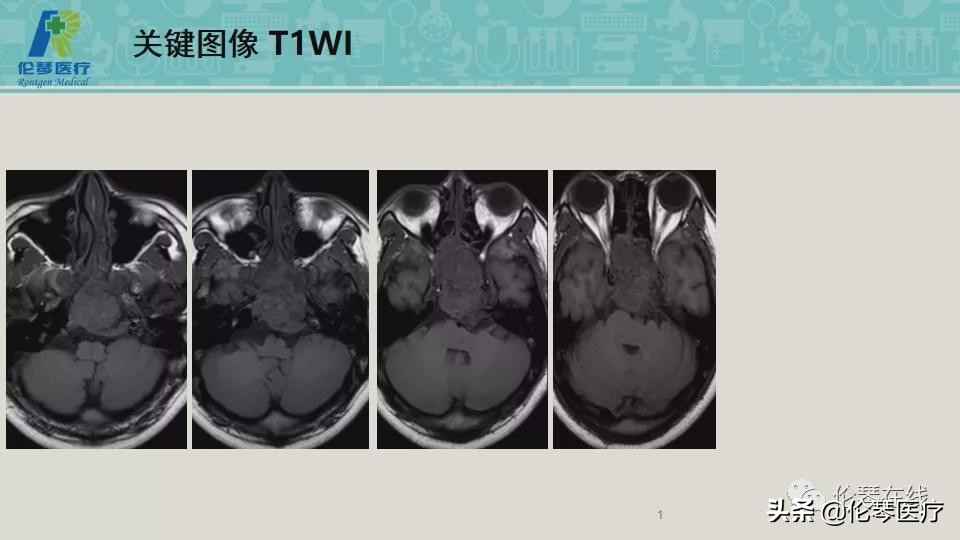

性别:男

年龄:21岁

主诉:头痛,双眼内收、外展受限8个月,加重2月

检查:CT扫描(影像图像见下方)